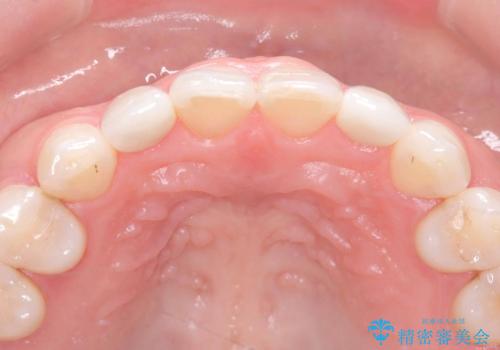

- 歯並びを矯正で整えたあと、上顎左右2番の歯(前歯の横の歯)の「矮小歯(歯が小さい状態)をオールセラミッククラウンで審美修復した症例です。

矯正によって歯並びはきれいに整いましたが、前歯全体のバランスをより自然で美しく仕上げるため、上顎左右2番にオールセラミッククラウンによる審美修復を行いました。

矮小歯はもともと歯が小さいため、削る量を最小限に抑えた負担の少ない治療が可能です。

また、自然な色合いや形になるよう、歯科技工士と連携し、写真を撮影しながら細かく色合わせを行い、周囲の歯になじむよう丁寧に仕上げています。